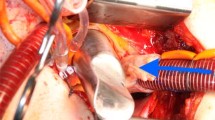

Video 1

Manually deforming the stent frame of a bio-sAVR: The video demonstrates how most bio-sAVR stent frames can easily be deformed by external forces. (MP4 1636 kb)